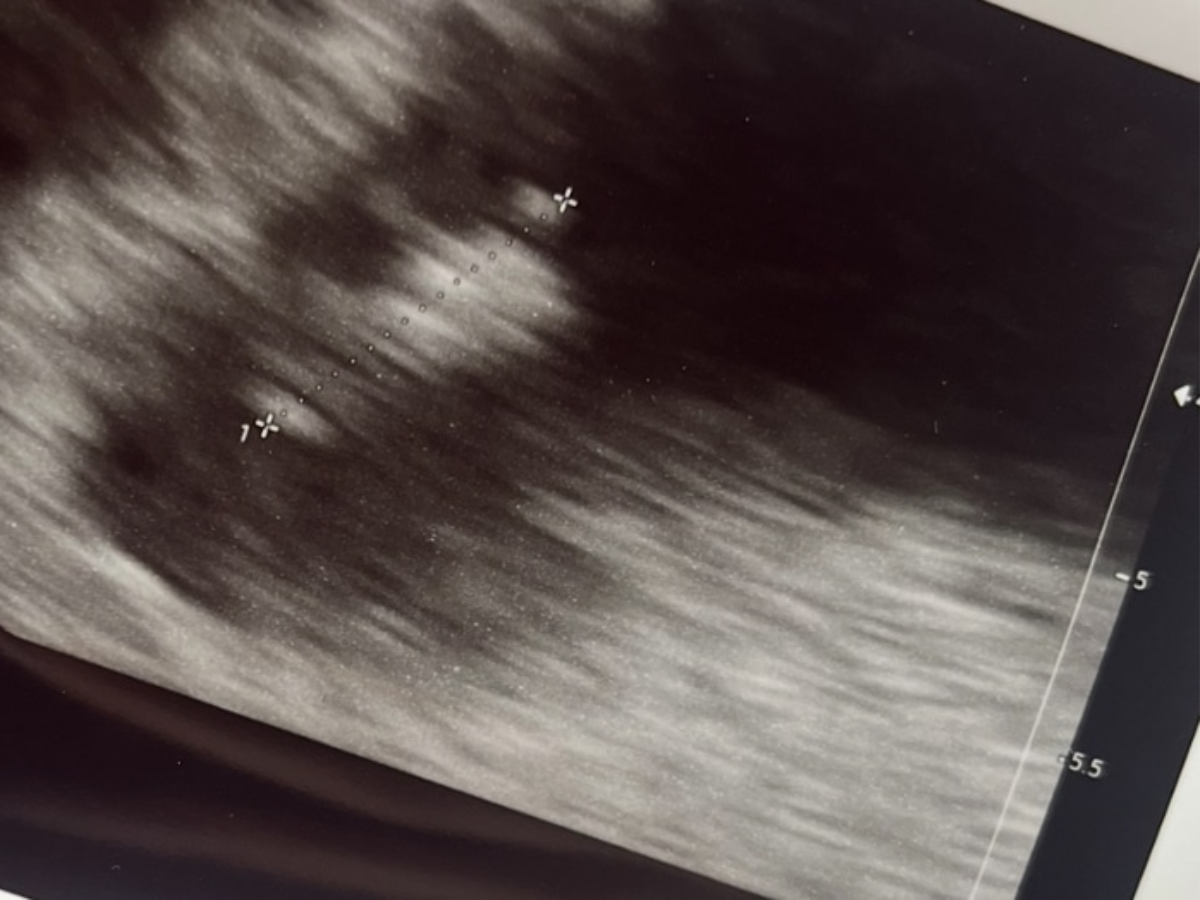

Met een flinke dosis spanning lopen we samen de praktijk in. Bas kent mijn gevoel niet. Hij begrijpt het niet. Wij hebben Sem samen, en dat is natuurlijk allemaal in één keer goed gegaan. Maar ik kan me herinneren als de dag van gisteren dat ik drie keer in zo’n stoel heb gelegen en te horen kreeg dat het hartje niet meer klopte. Toen het beeld aanging en ik dat knipperende lichtje op dat scherm mocht zien, biggelden de tranen dan ook over mijn wangen. Het was echt. Er groeide echt gewoon een klein mensje in mijn buik. Wat een wonder.

Als ik naar buiten loop en naar de echo kijk, maak ik mezelf en dit kleintje de belofte dat ik altijd alles in mijn macht zal doen om te zorgen dat hij of zij het mooiste leven krijgt dat ik kan bieden.”